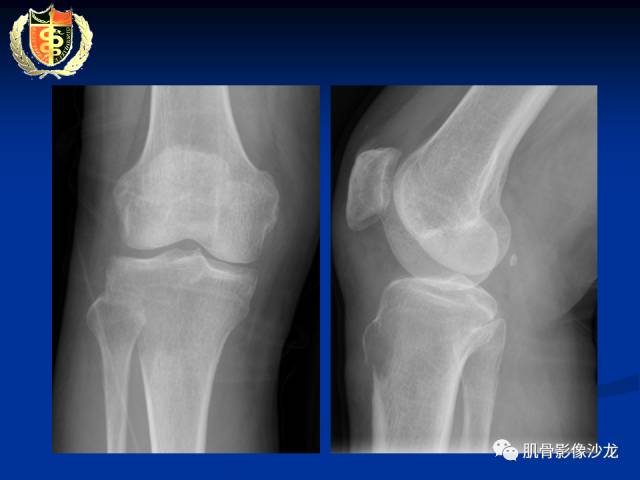

胫骨近端骨质破坏,边缘不清,破坏边模糊,骨皮质不完整,可见软组织肿块突破骨皮质外,病灶累及关节面下,无关节内累及,MRI病灶呈T2WI高信号,信号均匀,考虑:恶性肿瘤性病变,淋巴瘤先考虑,转移瘤及其他待排

内部密度和信号比较均匀,无钙化,无骨膜反应,骨质破坏边缘不清晰,软组织较明显,弥散受限,首先不能排除淋巴瘤

骨的基本形态保留的恶性肿瘤基本上也就尤文和淋巴瘤了

这俩年龄相差悬殊,所以比较容易鉴别